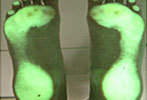

Korrektur der Fußfehlstellung

zu Behandlungsbeginn

nach 12 Monaten Behandlung

nach 24 Motanten Behandlung

Wer die Abdrücke seiner bloßen nassen Füße auf trockenem Fußboden oder als Sandabdruck betrachtet, wird feststellen, dass es zwischen rechtem und linkem Abdruck Unterschiede gibt. Das ist ein Beleg für ein Ungleichgewicht des Körpers.